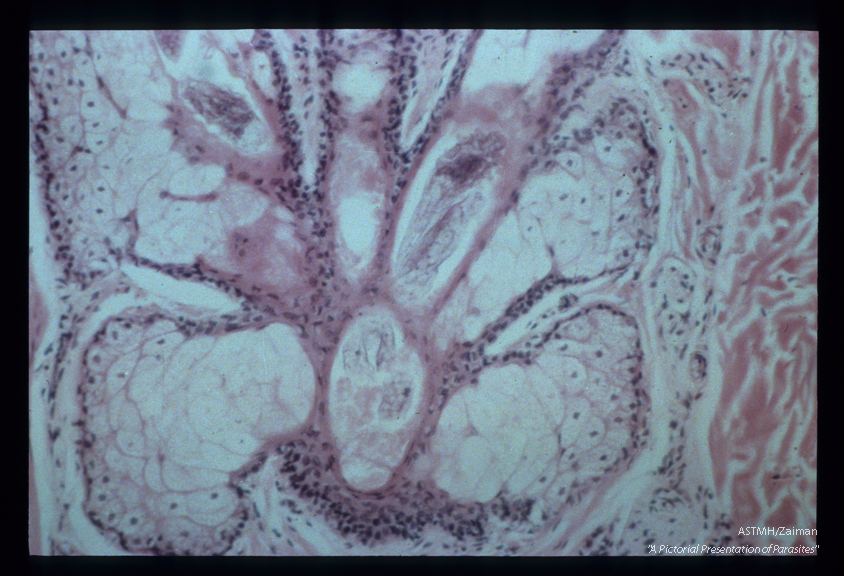

More or less complete longitudinal sections through three parasites in hair follicles.

Demodex folliculorum

Description: More or less complete longitudinal sections through three parasites in hair follicles.